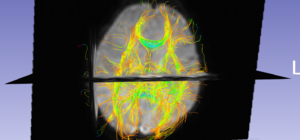

• DWI to DTI conversion was done using Slicer by utilizing the mask generated previously. We also performed a sanity check by overlaying glyphs and performing an approximate full brain tractography at this stage.

Glyphs overlaid on DTI

Full brain tractography for sanity check